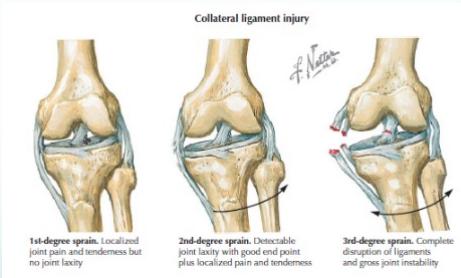

Clinical Signs

- Swelling

- Tenderness (in collaterals / origin / insertion)

- Stressing ligament is painful

- (In complete tears, stressing ligament may produce abnormal movement with little pain)